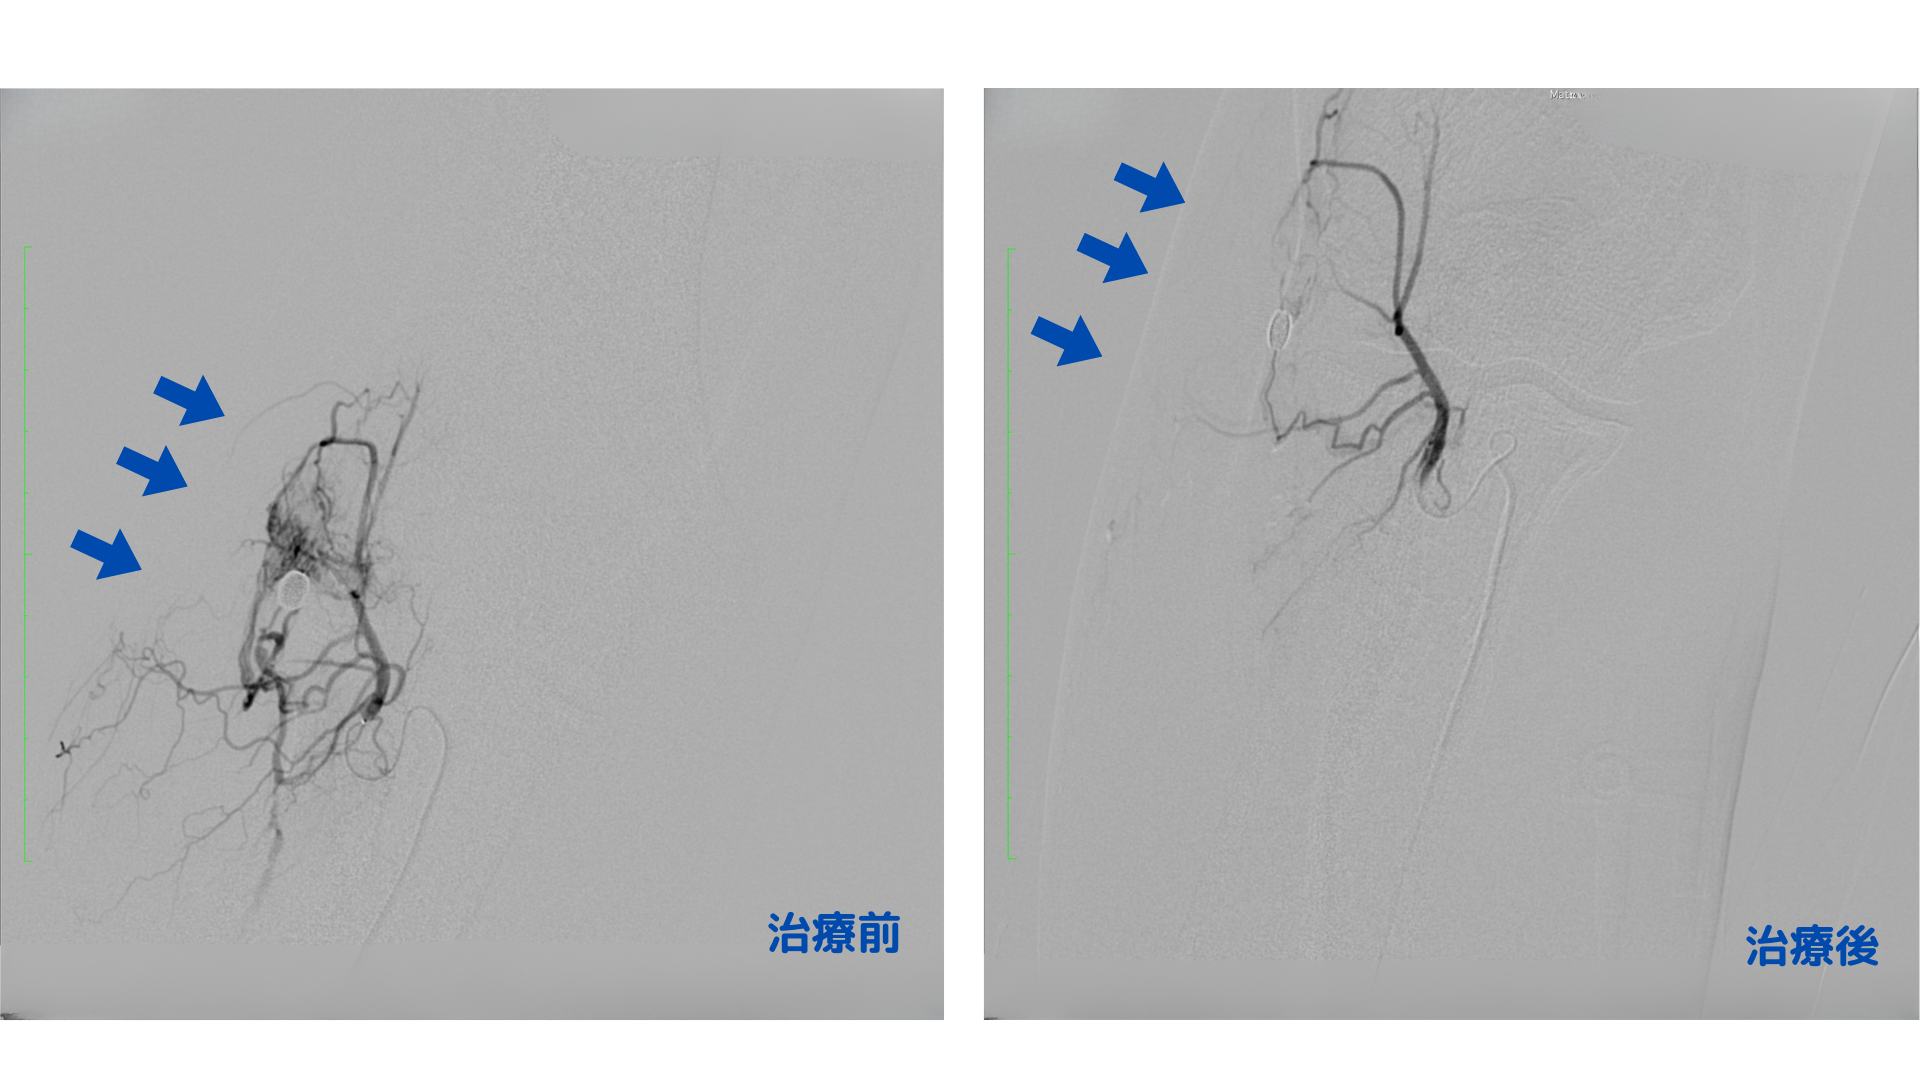

治療は、右手首の血管から極細のカテーテルを挿入し、痛みのある部位の近くまで進め、異常な血管のみを塞ぐ薬剤をピンポイントで投与することで炎症を抑え、痛みの改善を図ります。身体への負担が少ない日帰り治療です。治療直後から右肘の圧痛の軽減がみられました。